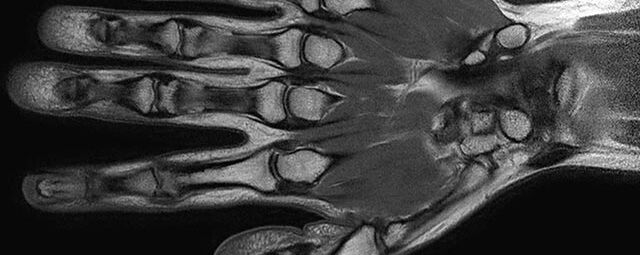

Gelenke

• Beurteilung von Knochen, Bändern und anderen Weichteilstrukturen der Gelenke nach Unfall.

• Arthrosediagnostik (Knorpelschaden)

• Ausbreitungsdiagnostik bei Gelenkentzündung, z.B. im Rahmen von rheumatischen Grunderkrankungen